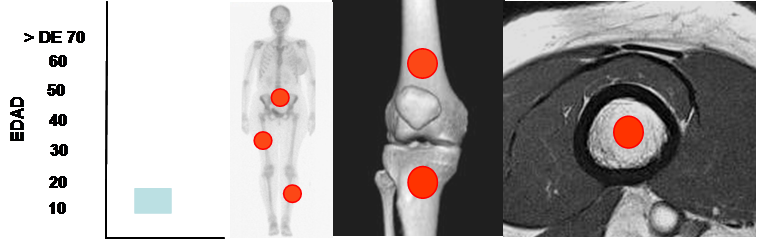

Fig 125. Sarcoma de Ewing.

Mayor frecuencia entre los 10 y 15 años. Predominio en huesos largos y el sacro.

Lesión metafisodiafisiaria, de ubicación central.